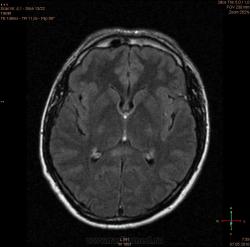

Болезнь Маркиафавы-Бигнами посмотри. На мой взгляд подходит.

Я заметил только 1 очаг в валике мозолистого тела. А для б-зни Маркиафавы-Бигнами более характерно несколько очагов дегенерации, в том числе и в полушариях.

Для болезни Маркиафава-Биньями считается патогноманичным центральная дегенерация мозолистого тела.

"Болезнь Маркиафава-Биньями – Болезнь Маркиафава-Биньями (Marchiafava, Bignami)- синдром при хроническом алкоголизме: энцефалопатия в форме центрального некроза corp.callosum (иногда и других комиссур). "

Я не против, действительно м.б. "Болезнь Маркиафава-Биньями". Особенно если нет динамики.

Но диф. ряд должен быть с опухолью. И если есть негативная динамика, тогда больше похоже на то, что в моз.теле не дегенерация, а "плюс-ткань" - обьемное образование. За октябрь сканов нет?

К сожелению первое исследование проводил ни я, а моя коллега, но контроль был за мной. Уже при первом исследовании, опухолевую принадлежность можно взять под сомнение, по скольку, даже допустим возьмем глиобластому это злокачественная опухоль из глиального ряда, т.е. должен быть тумор+отек=масс-эффект, ни того и не другого нет, ко всему этому сама локализация это валик мозолистого тела, а ни гемисфера, компенсации ни должно быть ни какой, клиника должно быть молниеносной и нарастающей.

Ко всему выше перечисленному могу добавить, видимо мою коллегу сомнения гложили, она провела исследование с контрастированием и получила тот же результат.